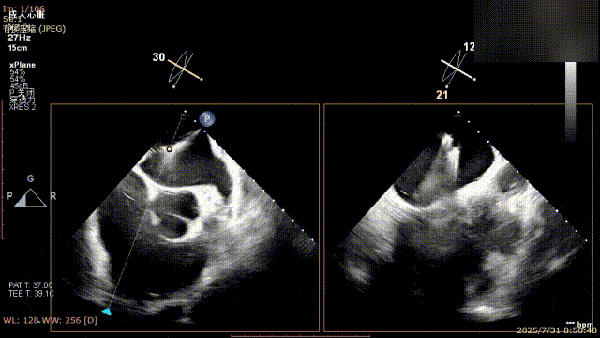

手术过程中,麻醉与围术期医学科副主任医师马金本确保麻醉过程平稳。心脏大血管外科主治医师董明亮穿刺股静脉置入血管鞘,并在心脏超声科梁皓主任及段福建教授TEE引导下,顺利穿刺房间隔,房间隔穿刺高度4.9cm。随后,在王安彪主任以及刘洋教授指导、心脏超声科梁皓主任TEE引导下,董明亮医师沿输送系统将延展呈“一字型”状态的国产夹合器送至左房,缓慢关闭夹合器并进行弹道测试。调整夹合器位置和方向后,董明亮医师再次将夹合器延展呈“一字型”完成跨瓣,避免发生腱索缠绕,成功捕获瓣叶后关闭夹合器,二尖瓣反流显著下降。夹合器完全解离后,超声示二尖瓣反流程度显著下降,残余反流0,平均跨瓣压差1mmHg,手术圆满成功。

解离后瓣叶及反流

解离后三维

平均跨瓣压差